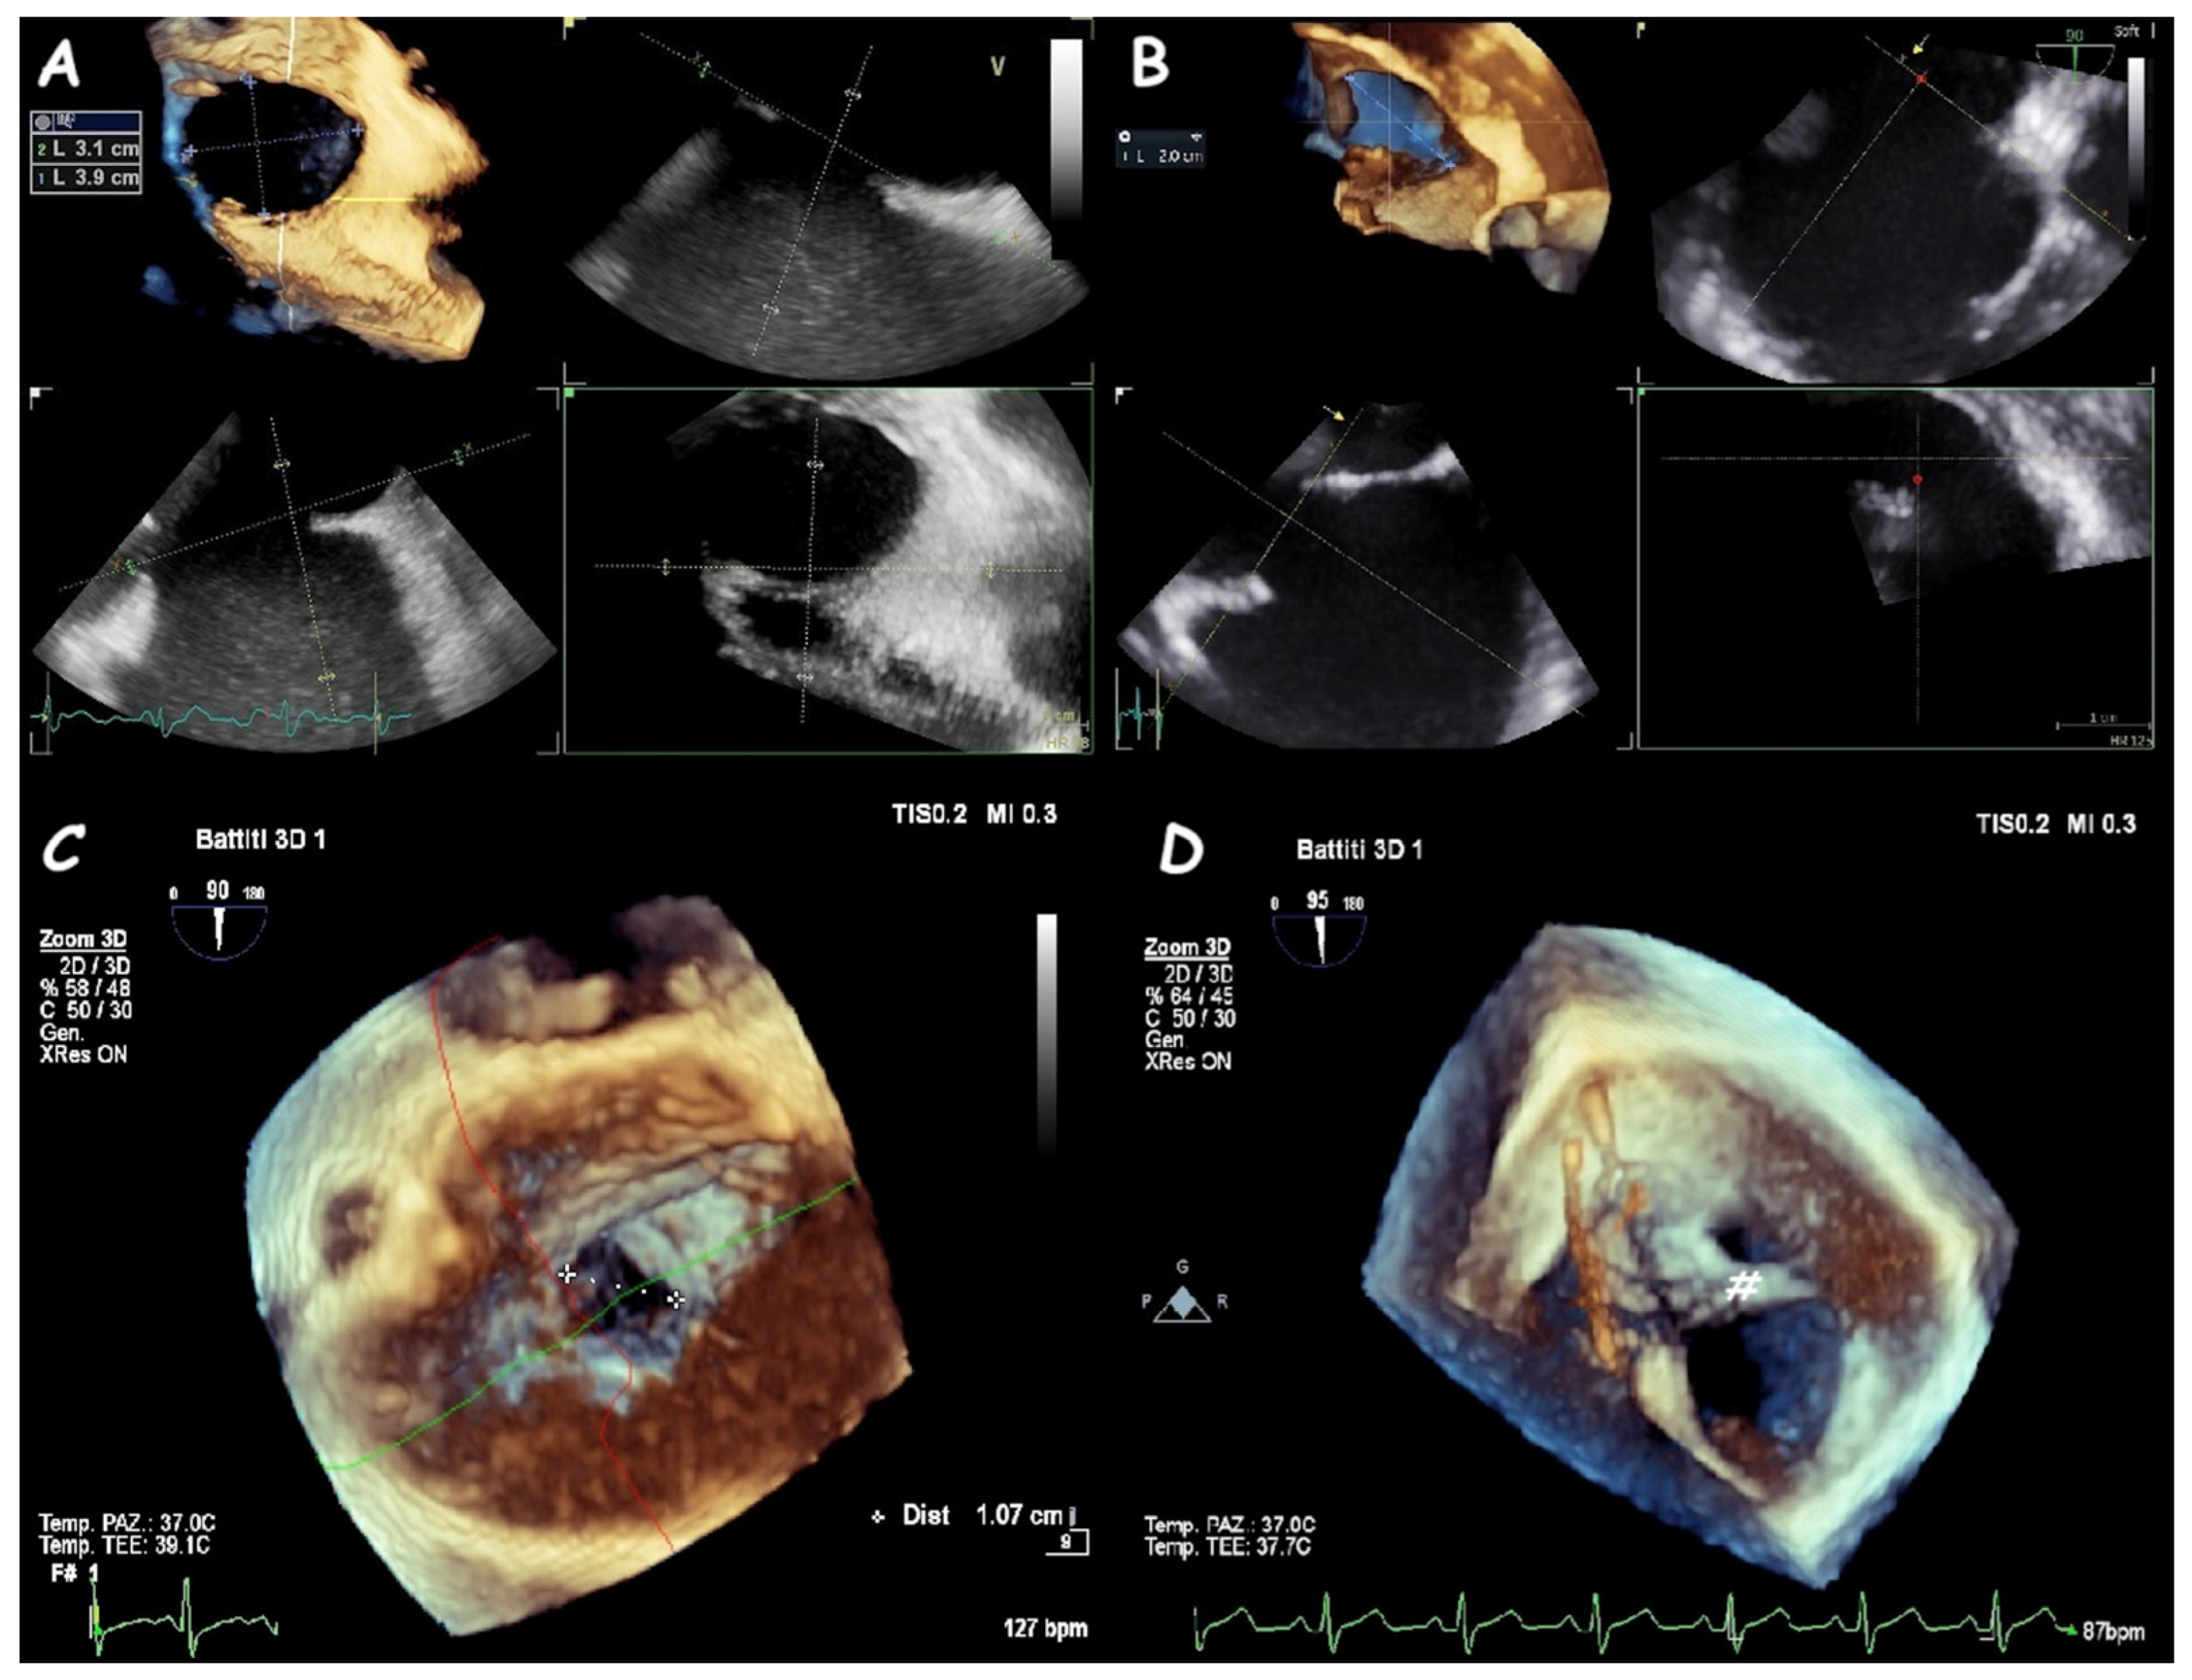

2. Atrial Septal Defect Closure